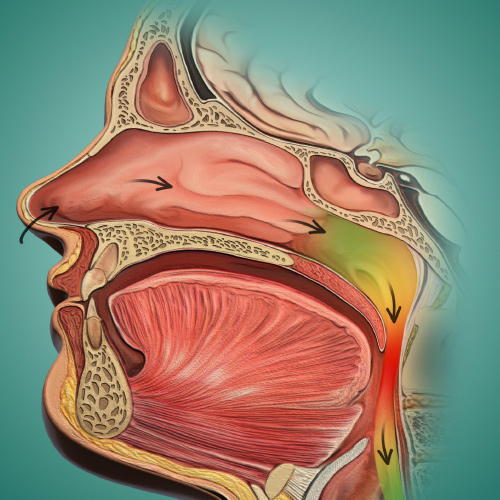

Oral Surgery Updates

Tuesday, October 1, 2024

This edition of the Compendium clinical eBook series features a continuing education (CE) article on the use of maxillomandibular advancement surgery for the treatment of obstructive sleep apnea in patients who are intolerant to continuous positive airway pressure (CPAP) or in whom CPAP or ...